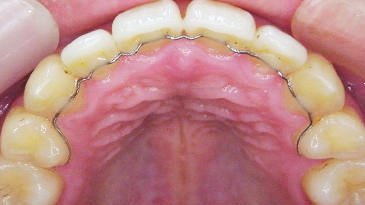

取り組み3:歯並びの改善

現代の子供たちは顎の成長が十分でなく、歯並びが悪くなることが多いです。当院では、「プレオルソ」というマウスピース型の装置を使った矯正治療を行っています。この装置は日中1時間と就寝時のみの装着で、口周りの筋肉を整え、歯並びを改善します。